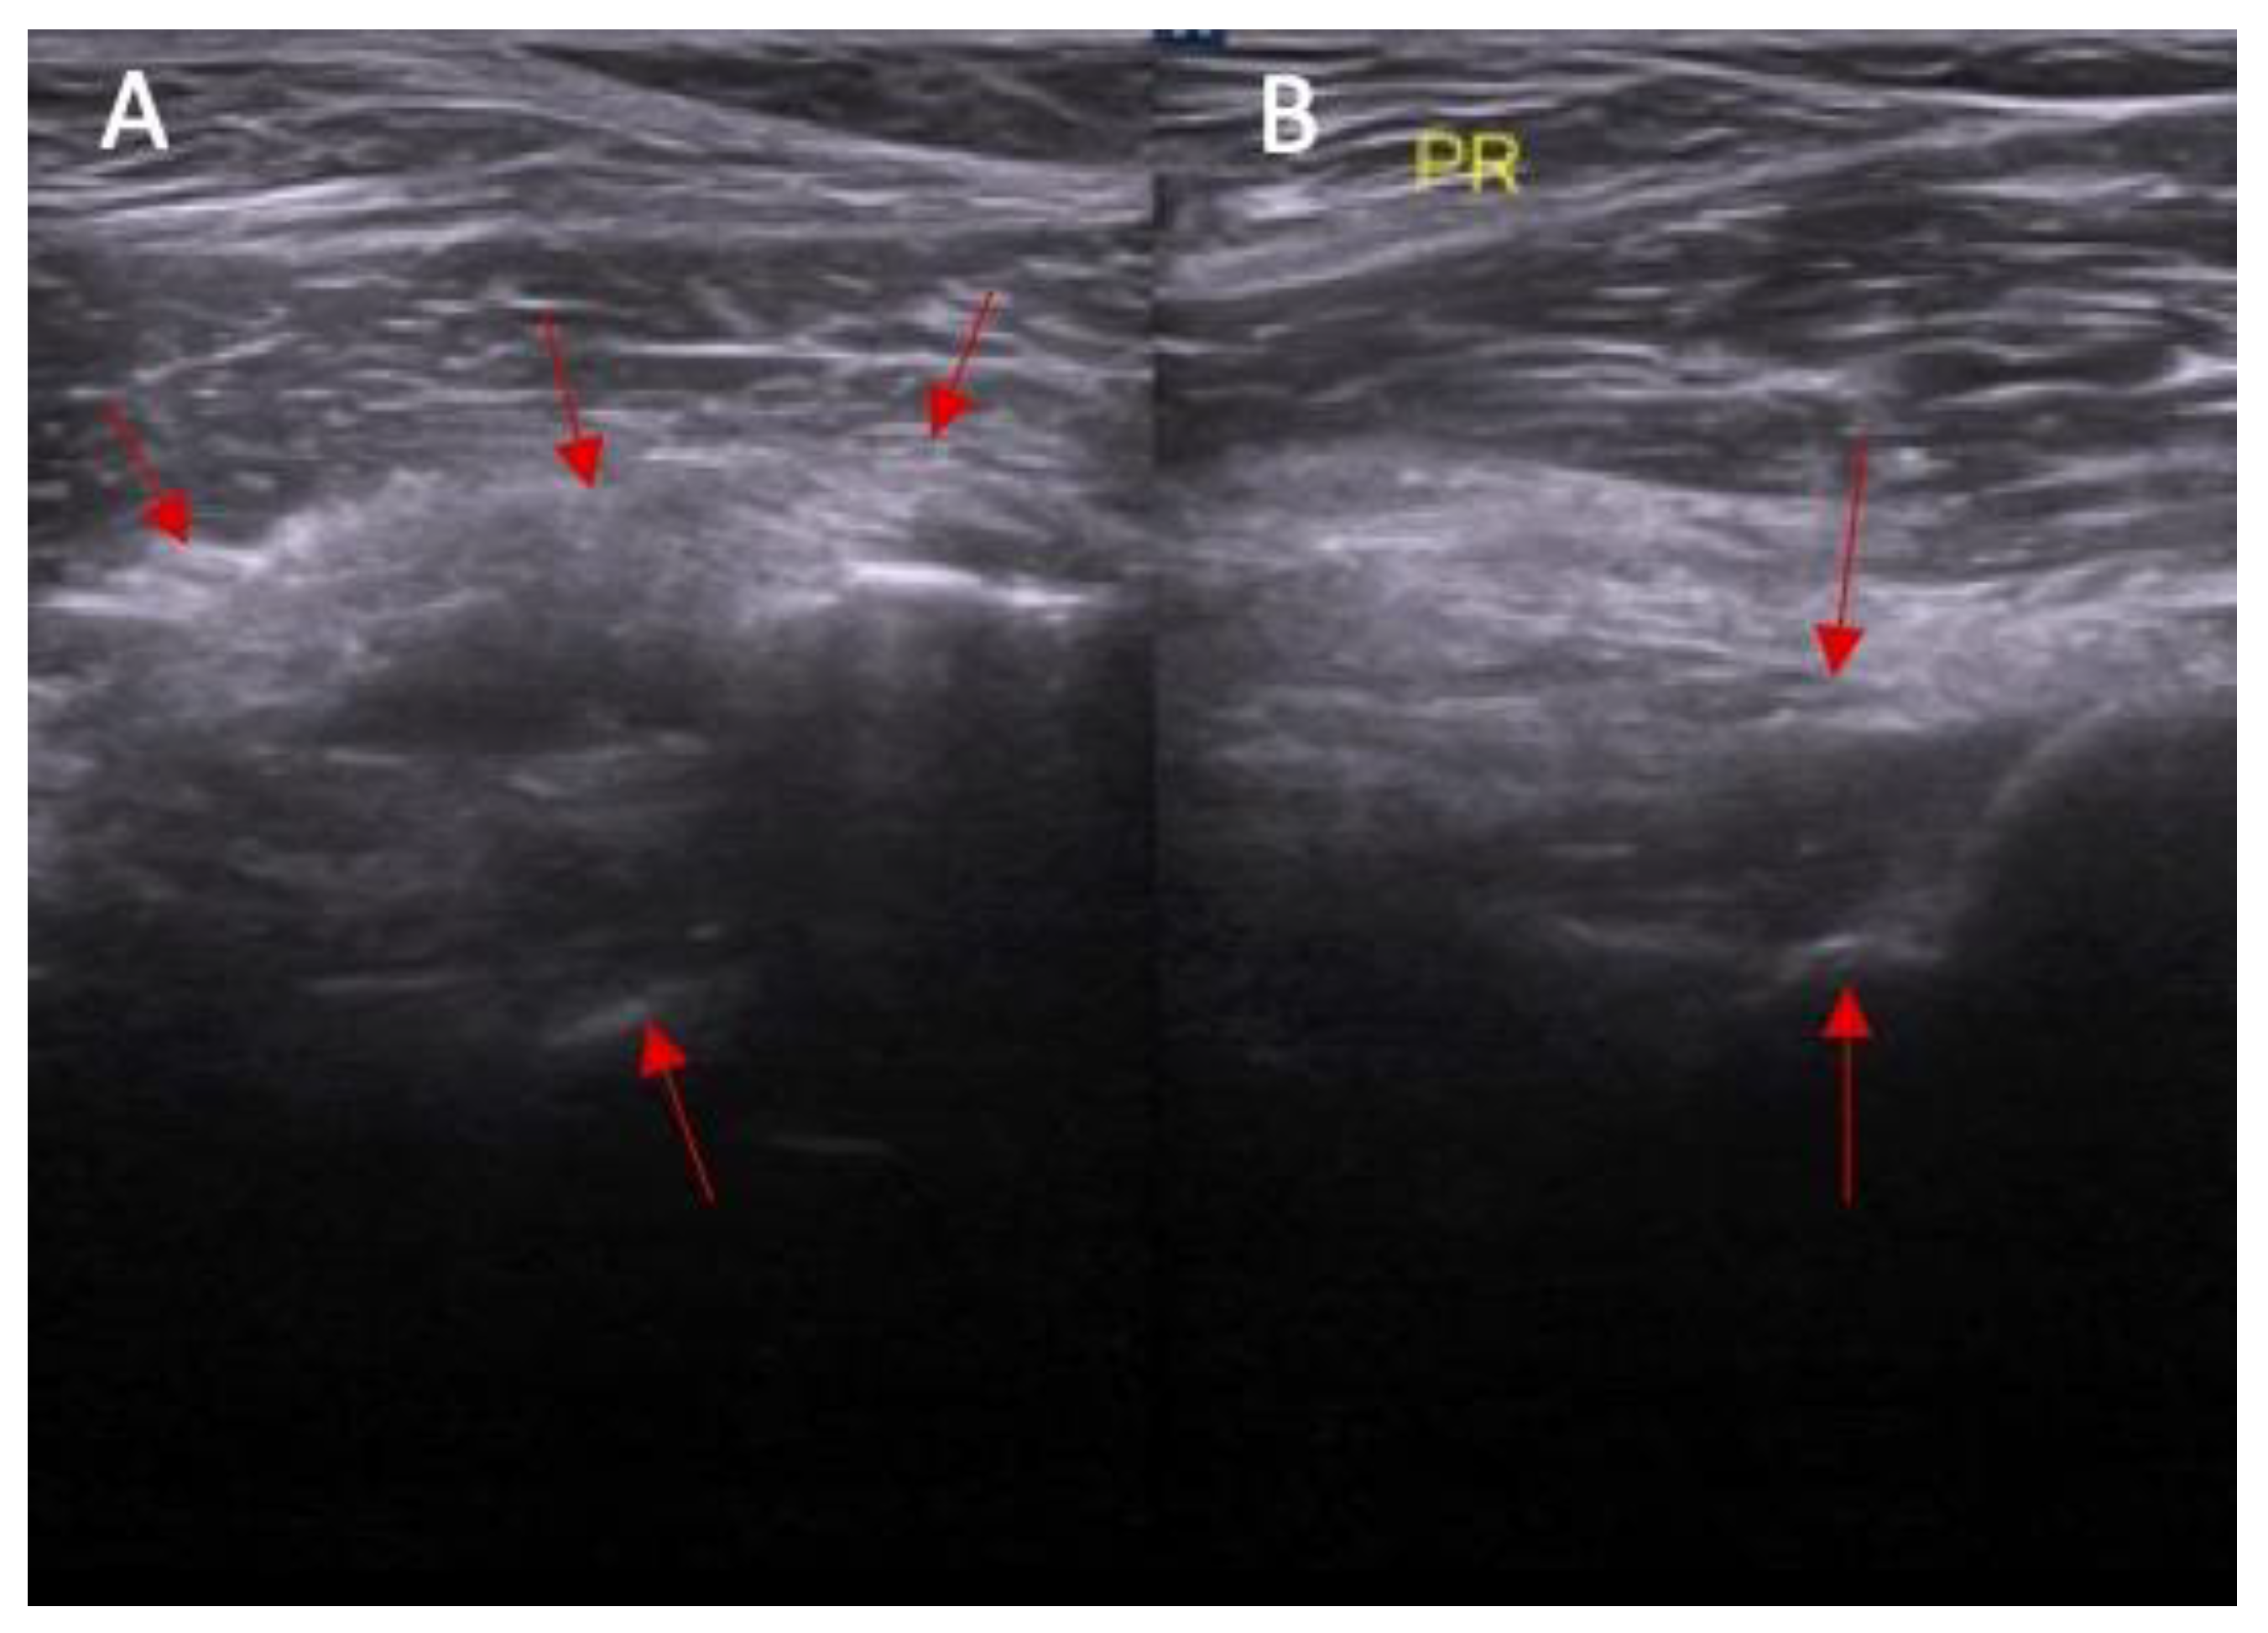

Swelling of the ACL/PCL on ultrasound was more common in patients with an ACL injury than in those without an ACL injury (88% vs. 0%, respectively, and p < 0.0001) (Figure 6 and Figure 7). OR = incalculable.

Figure 6.

(A) Ultrasound view of swelling/scarifications of the ACL/PCL compartment with change of the morphology of the posterior joint capsule complex marked with the arrows and (B) normal view. PR—right.